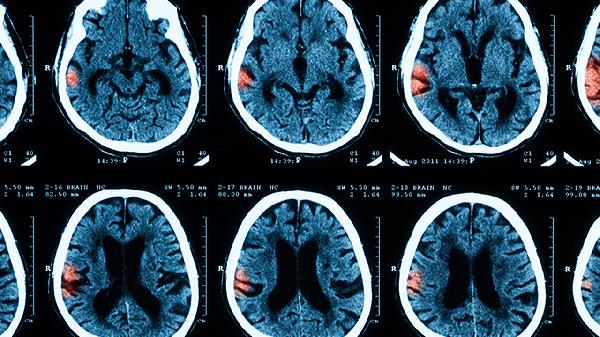

小儿急性脑膜炎症状包括发热、头痛、呕吐、颈部僵硬、意识障碍等。发热是常见症状,体温可能迅速升高至39℃以上。头痛通常较为剧烈,伴随恶心和呕吐。颈部僵硬表现为颈部肌肉紧张,患儿难以低头。意识障碍可能表现为嗜睡、烦躁或昏迷。部分患儿还会出现皮疹、抽搐等症状。

急性脑膜炎属于严重疾病。多数情况发病急骤且危害大,若不及时治疗可能导致生命危险或遗留后遗症,主要风险有颅内压升高...